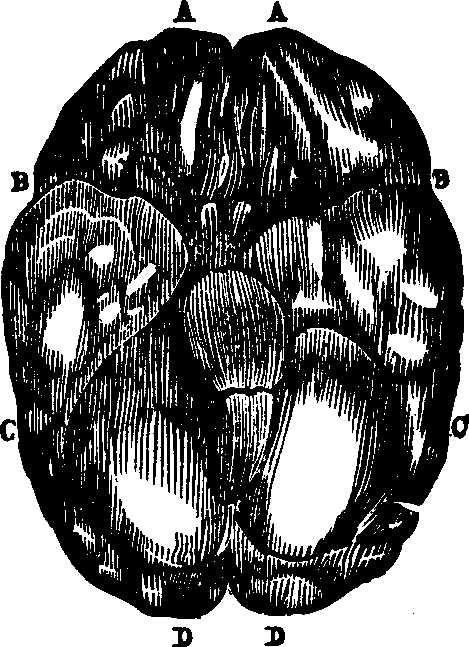

converted into a homogeneous fluid, which pervades every part of the body,

is the basis of every tissue, and which is termed the blood. This

varies in color and composition in different animals. In the polyp the

nutritive fluid is known as chyme, in many mollusks, as well as

articulates, it is called chyle, but in vertebrates, it is more

highly organized and is called blood. In all the higher animal types it is

of a red color, although redness is not one of its essential qualities.

Some tribes of animals possess true blood, which is not red; thus the blood

of the insect is colorless and transparent; that of the reptile yellowish;

in the fish the principle part is without color, but the blood of the bird